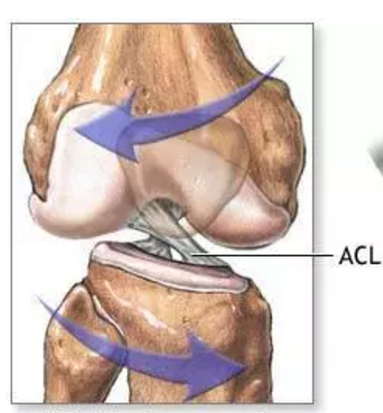

膝前十字靱帯 (ACL)損傷とは 膝には、関節の動きをコントロールする4本の靱帯があります。 前十字靭帯はそのうちの一つで、膝が伸びすぎないように抑えたり、膝の前ずれや捻りの方向への動きを制御をしています。 ジャンプの着地や急な方向転換、相手Acl術後の固有感覚の回復過程について,術後6か月で 正常な機能に戻るという報告がある4).今回の総軌跡長の 変化では,男女とも経時的に有意な減少を認め,術後6か 月以降に安定する傾向を示し,同様の結果が得られたと考 acl再建術後患者のスポーツ復帰において、テーピング、装具または両方の併用、いずれが推奨されるか? 確認 7 acl再建術後のスポーツ復帰基準において筋力、関節可動域、動作いずれが判断材料として推奨されるか? 確認 8